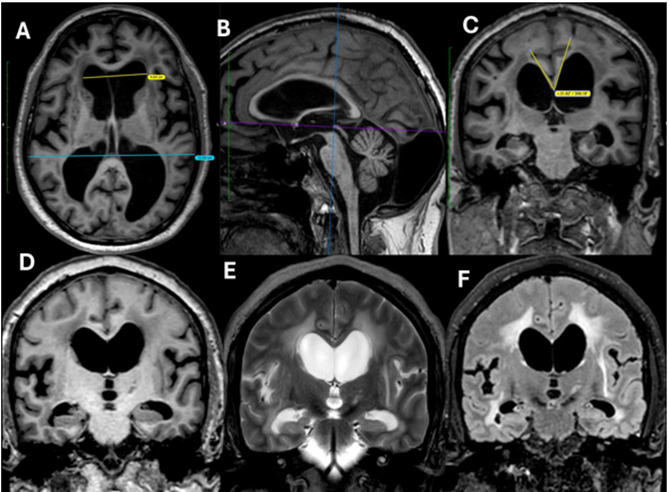

The case definitions of MRI findings applied in this study are summarized in Box 1 and representative images depicted in Figure 1.

Figure 1: Axial T1-weighted image (A) shows ventriculomegaly out of proportion to cortical sulcal dilatation, with an Evans’ index of 0.39. Sagittal T1-weighted image (B) demonstrates the reference planes for callosal angle measurement: the horizontal line passing through the anterior and posterior commissures (AC–PC line) and the vertical line perpendicular to it, passing through the posterior commissure. Coronal T1-weighted image (C), corresponding to the vertical reference plane, shows a narrowed callosal angle of 52°, flattened high-convexity sulci, periventricular hypointensities, and widened Sylvian fissures, suggestive of idiopathic normal pressure hydrocephalus (iNPH). Coronal T1 (D), T2 (E), and FLAIR (F) images demonstrate periventricular T2/FLAIR hyperintensities, a narrow callosal angle, and flattened convexity sulci.